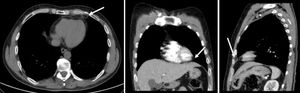

A healthy 50-year-old man was admitted to the emergency department for sudden intense pain located in the lower left anterior part of the chest, worsened by deep inspiration and with 10 hours of duration. The patient had had no similar episodes previously. He presented with tachypnea (29 cpm), tachycardia (heart rate 110 bpm) and diaphoresis. The electrocardiogram showed sinus tachycardia, without ischemic changes. Results of blood studies, arterial blood gas testing, cardiac markers, transthoracic echocardiogram and chest radiography were normal. Thoracic CT (Figure 1) showed an ovoid encapsulated mediastinal (epipericardial) fatty lesion in the left cardiophrenic angle with a soft tissue rim and intrinsic and surrounding soft tissue stranding, without pleural effusion. During hospitalization, the patient remained stable under analgesic therapy and was discharged with medication for symptomatic relief (non-steroidal anti-inflammatory drugs). After two and five months, thoracic CT showed a reduction of the lesion (Figures 2 and 3).